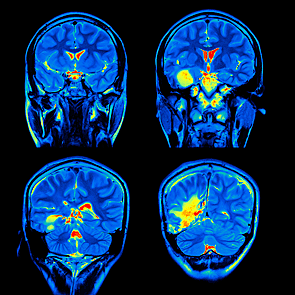

• Periodo contemporáneo (desde 1975)

Periodo contemporáneo (desde 1975)

Este periodo está marcado por el surgimiento de las imágenes cerebrales como la tomografía axial computarizada (TAC), que supuso una revolución en las neurociencias.

Con los avances se ha podido comprobar que existen otras áreas que no son “clásicas” en la neuropsicología y que participan en procesos cognitivos.

• La investigación avanza de la mano de imágenes no ya anatómicas, sino funcionales.

La investigación avanza de la mano de imágenes no ya anatómicas, sino funcionales.

La resonancia magnética funcional (RMf) y la tomografía por emisión de positrones (TEP). Estas técnicas permiten observar la actividad cerebral durante la realización de actividades cognitivas como hablar, leer, pensar en palabras, etc.